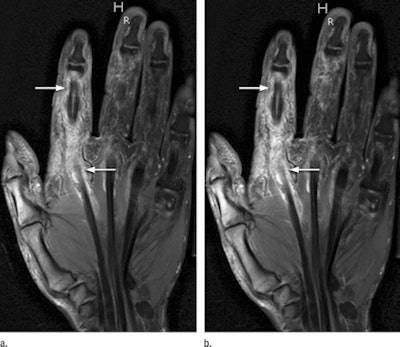

T1-weighted, fat-saturated, postcontrast 3-tesla MRI shows a half dose (a) and a full dose (b) of gadobenate dimeglumine in a 47-year-old man with early rheumatoid arthritis. The tendon sheath of the flexor tendons illustrates increased synovial enhancement, with tenosynovitis of the second flexor tendon scored as grade 3 (arrows) at both half dose and full dose. Images courtesy of Radiology.Despite the disparity in contrast-to-noise and signal-to-noise ratios between the dosages, the diagnostic quality of the images was not affected, according to the authors. No region of synovial inflammation seen on full-dose contrast-enhanced MRI was missed at half dose.

"These results demonstrate that no diagnostic information that would be relevant for diagnosing and staging rheumatoid arthritis, therapy planning, therapy monitoring, or follow-up examinations was missing from half-dose images," the authors wrote.